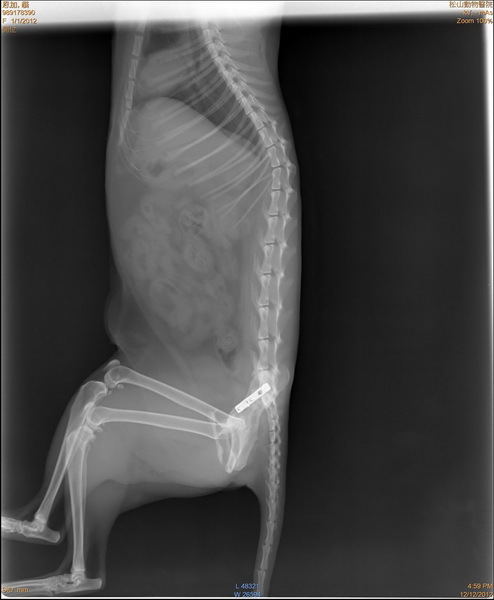

主題: 松江市場車禍骨盆腔骨折的虎斑白 申請者姓名: 蔡葦澄 花色: 申請日期: 2012-12-22 14:46:33 申請者部落格: 申請者臉書網址: 所在縣市/合作醫院: 台北市/恩加動物醫院 治療費用: 6500元 需求人數: 15人 已結案 (2013-08-06 13:46:15) 報名人員: Jill(已付款)、簡絜(已付款)、簡絜(已付款)、莊孝國(已付款)、李安妮(已付款)、Uu、火鳳貍(已付款)、Bella(已付款)、Weili Chang(已付款)、Jess(已付款)、CrystalBall(已付款)、黃先生、zofia(已付款)、Grace Kulai(已付款)、Weiwen Tu(已付款)、蔡郁亭、ming(已付款)、hero178(已付款)、 候補人員: 動物病情說明: 松江市場被車撞的貓咪,骨盆腔骨折被送往收容所,掃晶片發現是市政府TNR的貓咪,由晶片找到負責志工,但已失聯,動保處也沒有相關的訊息,貓咪還需要持續醫療,放任不管直接回置肯定喪命,很謝謝TNR協會的幫忙,讓這隻貓咪得到好的醫療,現在已經康復回置,也請市場的愛心媽媽看顧,醫療住院的費用還請大家幫忙。